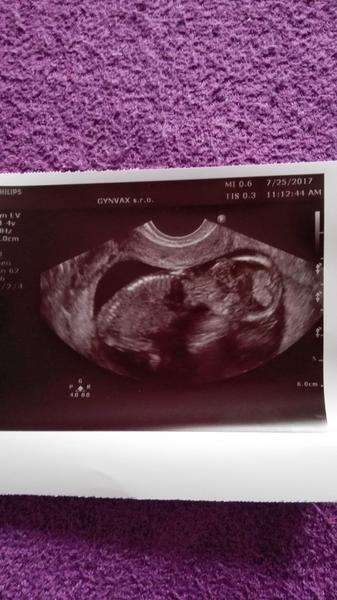

Ahojte kočky tak dnes som 32DC (16DPO) a teraz som už konečne pokojnejšia a začínam sa tešiť že čiaročka je silná....no kuknite